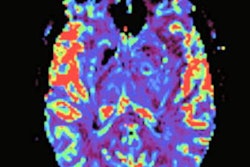

The company will use the funds for the development, translation, and commercialization of software for clinical use in perfusion MRI to better identify brain tumor burden and evaluate treatment response. The researchers plan to add artificial intelligence (AI) capabilities to streamline and automate processing.